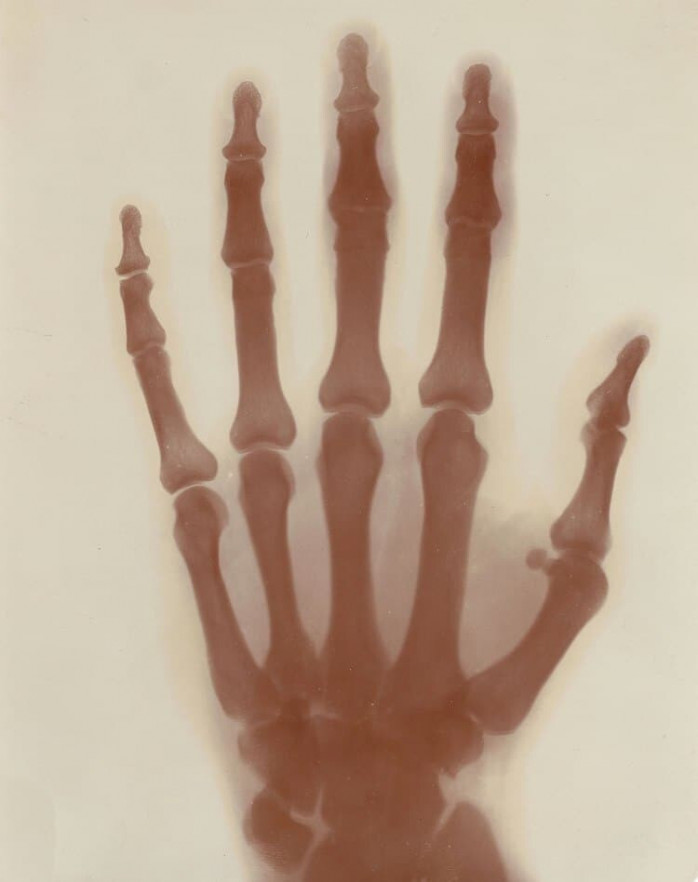

После публикации Рентгена Тесла продолжал узнавать больше о рентгеновских лучах. Он провел свои собственные эксперименты, создав высокоэнергетическую вакуумную лампу, которая работала на выходе катушки Тесла — его самого известного изобретения. Назвав свои снимки «теневыми диаграммами», Тесла делал их, используя самую простую модель, которую смог найти, — самого себя. Рентгеновские снимки его стопы (с металлическими частями его ботинка ) и его руки являются отличным свидетельством его работы.

Но на этом вклад Теслы в мир радиологии не закончился. Он быстро указал на пользу рентгеновских лучей в области медицины. Отметив, что рентгеновские лучи отображают более плотные тела иначе, чем менее плотные, он описал, как эту технологию можно использовать для поиска посторонних предметов в теле или даже для выявления заболеваний легких.